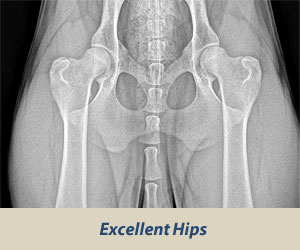

Bedrový kĺb tvorí: kĺbová jamka (acetabulum), väzy, bedrový kĺb, šľachy a svaly. Hlavica stehennej kosti je uložená v kĺbovej jamke, veľmi pevne zapadá do kĺbovej jamky. Na povrchu jamky a kĺbovej hlavice je chrupavka. Zabezpečuje pružnosť kĺbov a chráni kosti pred opotrebovaním. Záťaž je rovnomerne rozložená na celú plochu kĺbu a jamky.

Choroba je spôsobená nedostatočným vývinom kĺbovej jamky a bedrového kĺbu. Nerovnomerný rast kostí spôsobí poškodenie chrupavkovitých častí. Zmeny na bedrových kĺboch je možno dobre pozorovať na RTG snímkach. DBK postihuje najčastejšie veľké a obrie plemená, môže sa však vyskytovať u ktoréhokoľvek plemena.

Hodnotí sa tvar kĺbovej jamky, hlavice kĺbu, vek zvieraťa, Norberg-olsonov uhol. Výsledný stupeň rozvoja DBK sa stanoví predovšetkým podľa Norbergovho uhla v stupňoch.

Výsledok (nález) sa označuje číslami 0-4 a písmenami A-E a je zaznamenaný pre každú končatinu zvlášť.

0 A – negatívny anatomická pravidelnosť, žiadne príznaky dysplázie 105° a viac